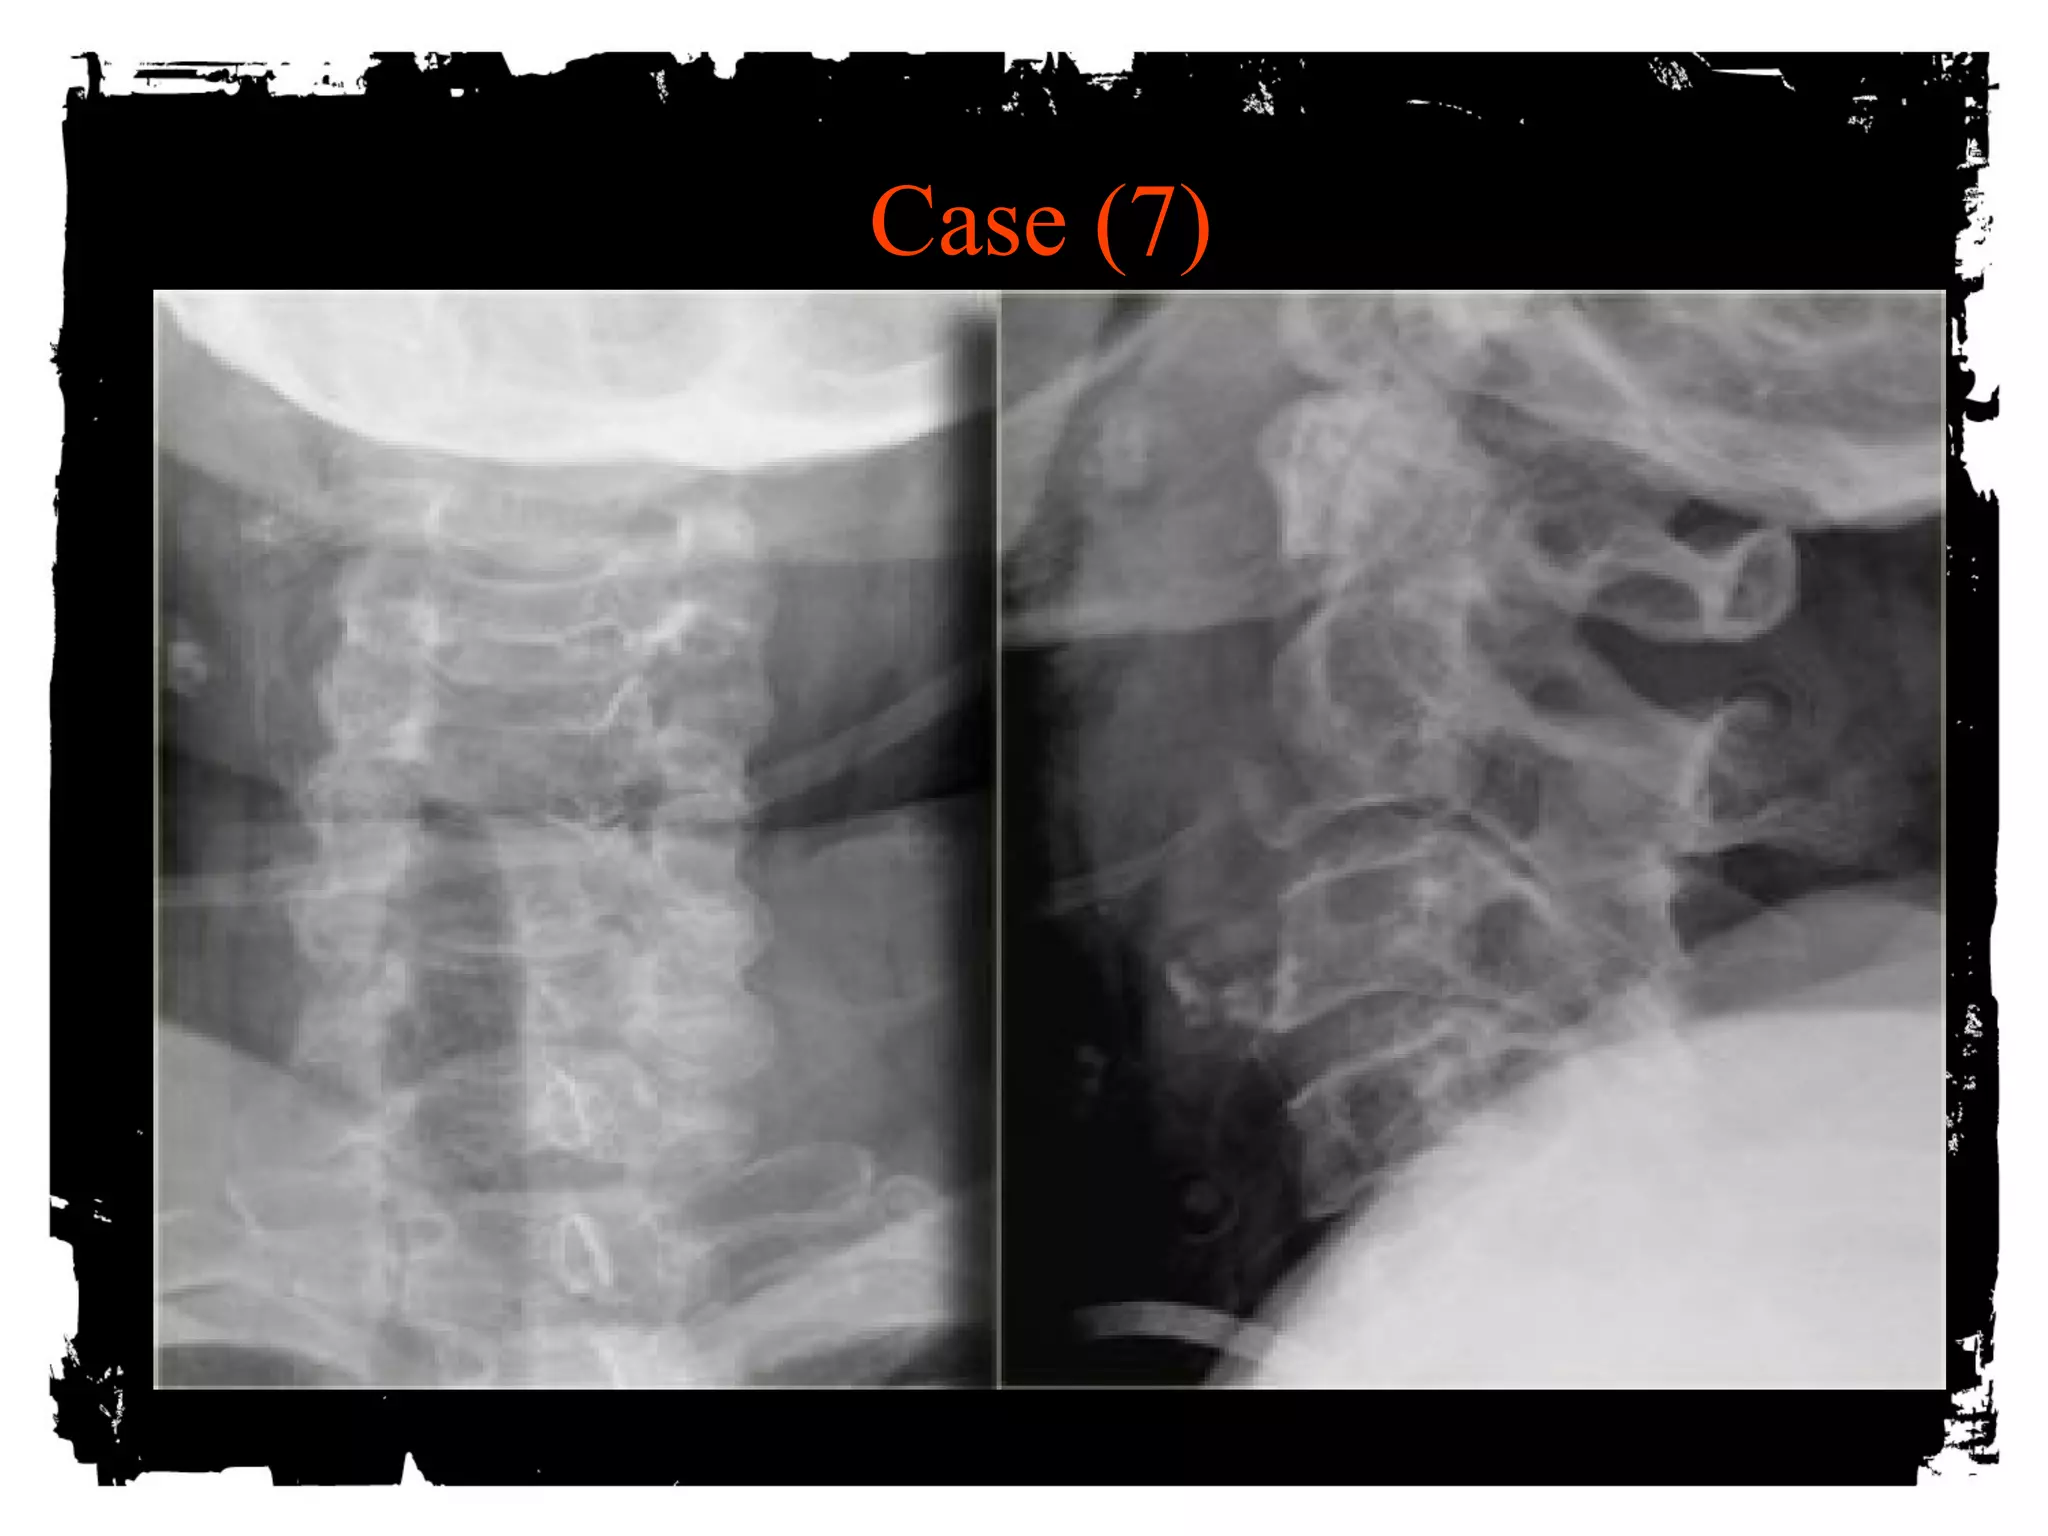

Case (7)

CLICK HERE TO ADD TEXT

Extension Teardrop Fracture

ALL pulls bony fragment away from inferior aspect

of the vertebra because sudden extension

Fragment is true avulsion x fragment from flexion

teardrop (compression)

Lower cervical spine

Central cord syndrome (buckling of ligamenta flava

into spinal canal)

Stable in flexion; highly unstable in extension